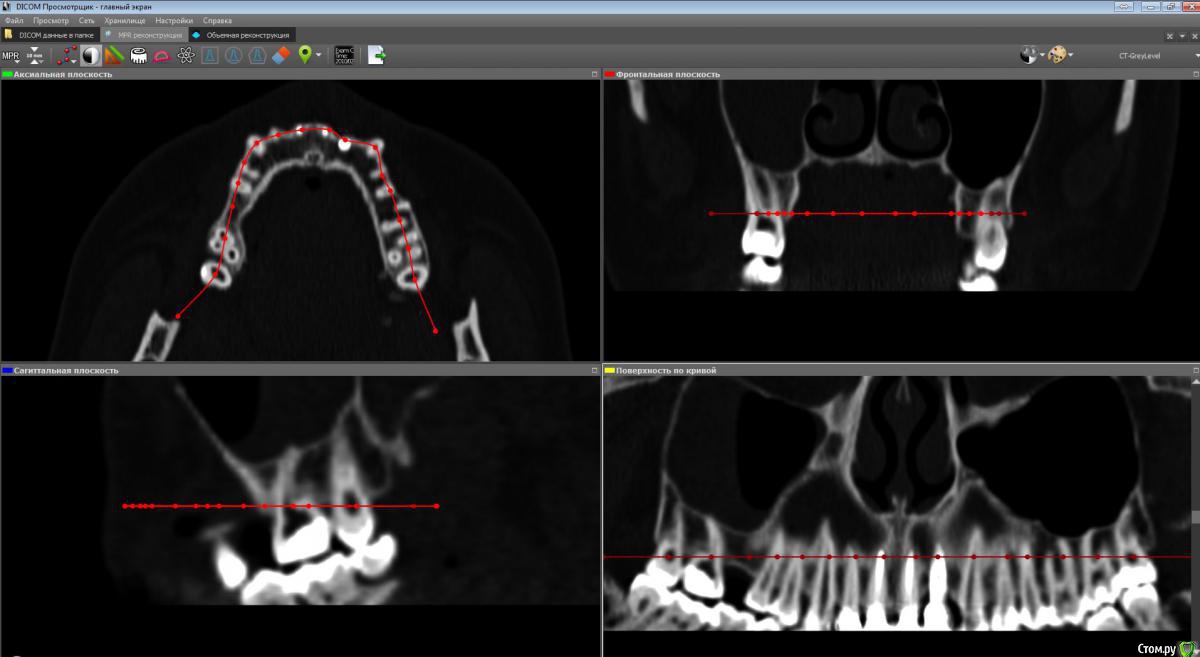

Лисица Опубликовано 26 июля, 2015 Автор Поделиться Опубликовано 26 июля, 2015 (изменено) Вы же не думаете, что Вам назначат а/б терапию по интернету? Я просто не знаю, исходя из каких показателей она назначается. Поэтому осведомилась на всякий случай. Итак, сходила я сегодня на КТ. И по ходу мне сделали что-то не то... Когда я обратилась в клинику, я уточнила, что мне нужно КТ для эндодонтии, чтобы видно было каналы, с достаточным разрешением, чтобы было видно зубы и их корни, входящие в верхнечелюстной синус. Администратор клиники уточнила у врача и сказала, что мне нужно заказывать не КТ верхней челюсти, а КТ пазух. У рентгенолога я также повторила все описанное, рассказала, что при лечении каналов вчера была продырявлена пазуха, уточнила, будут ли видны как следует зубы и их каналы, меня заверили, что "все будет". Причем у врача, судя по описанию на сайте клиники, была ординатура по хирургии в медико-стоматологическом университете, так что он, уж наверное, понимал, что мне нужно. В итоге я получила пленку со снимками формата чуть ли не А3 и диск. На пленке все зубы были просто белыми и коронки видны не целиком. Заключение: в правой верхнечелюстной пазухе уровень жидкости, острый правосторонний гайморит.Думала, может в программе можно будет увеличить разрешение. Но похоже, что нет... или я просто ламер? Зубы просто размытые и белые... Прилагаю сделанные мной скриншоты, как мне кажется, наиболее показательные... Если нужно другие "виды", то скажите какие, или такие снимки вообще ни о чем? Программа просмотра называется Philips DICOM Viewer R3.0-SP03. Аппарат был не местный "на голову", а здоровый, куда заезжаешь в лежачем положении. Изменено 26 июля, 2015 пользователем Лисица Ссылка на комментарий

Лисица Опубликовано 27 июля, 2015 Автор Поделиться Опубликовано 27 июля, 2015 К сожалению, предыдущие сообщения уже не редактируются, но я наконец разобралась с правильным просмотром через DICOM Viewer Теперь у меня есть приличное 3D и я беру обратно свои слова насчет "неправильной" КТ %) Хотя все же нужно было делать челюсти, лобные доли мне как бы совсем ни к чему, а вот нижняя челюсть пригодилась бы...Думаю, как бы выложить DICOM-данные. Ссылка на комментарий

Лисица Опубликовано 27 июля, 2015 Автор Поделиться Опубликовано 27 июля, 2015 Вот что я нарисовала, почти ортопантомограмма Но четкости добиться не выходит все же. Ссылка на комментарий